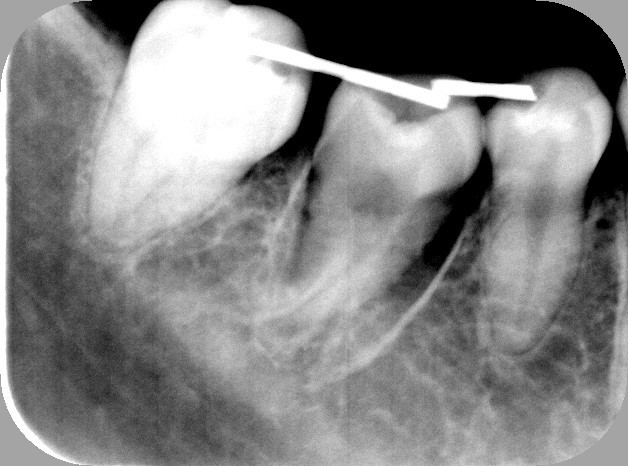

3.上の親知らずを下へ移植直後